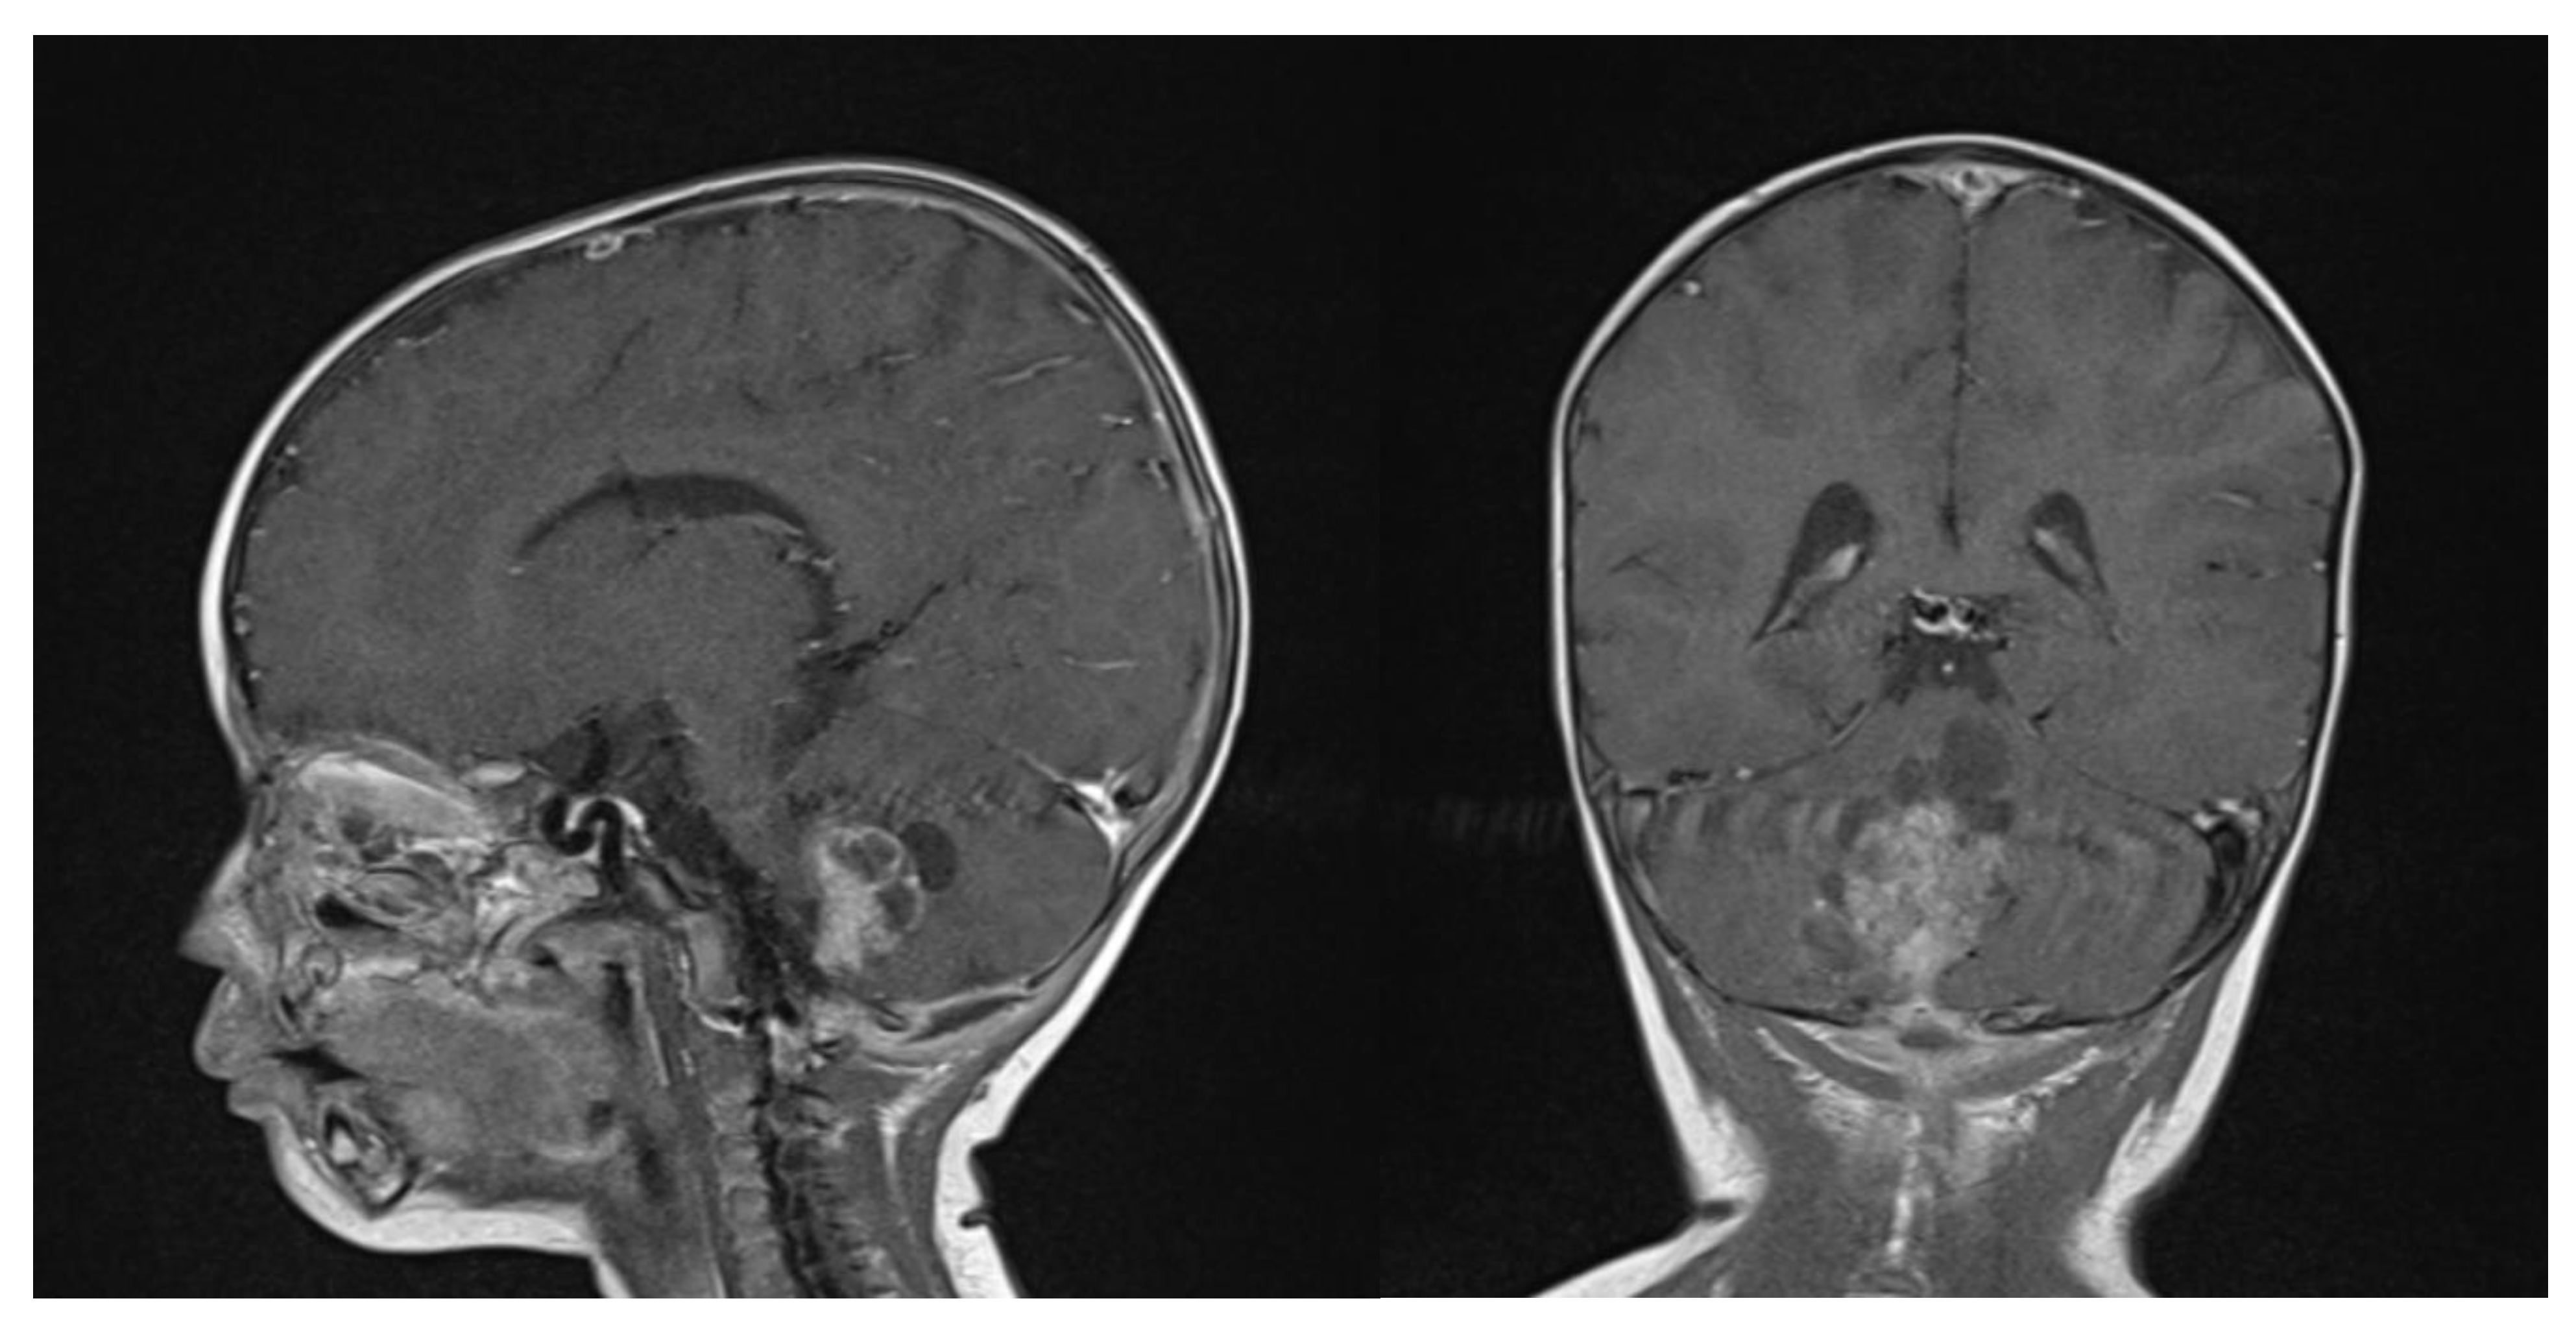

At the last follow-up at 23 months old, the patient did not show any sign of recurrence, with stable enhancing tissue on the floor of the IVth ventricle. Clinical examination was normal, as was global development (as stated by a consultant infantile neuropsychiatrist) (Figure 7). No adverse or unanticipated events were assessed. In this particular situation, local proton therapy (according to the ACNS0333 trial) was recommended [24].

Figure 7.

14 months post-operative gadolinium T1 sagittal and axial sequences, showing no signs of recurrence.